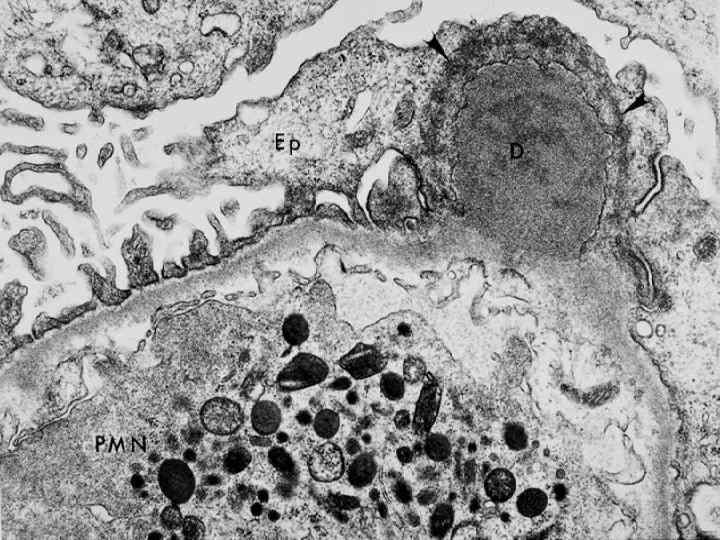

Нейтрофил Диффузный генерализованный эксудативно-пролиферативный гломерулонефрит, субэпителиальные депозиты ( «горбы» )